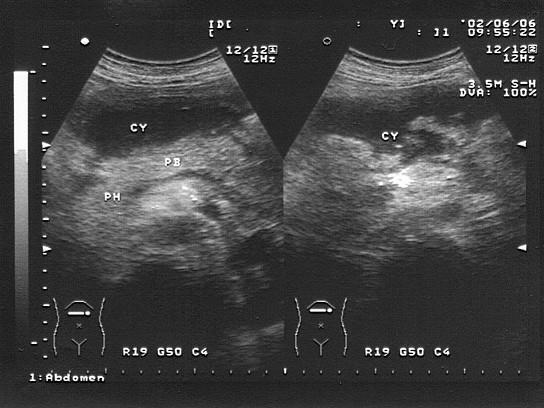

问题 女,20岁,上腹痛并呕吐,入院诊断“急性胰腺炎”。结合超声声像图,诊断为?(?)

选项 A.胰腺脓肿 B.胰腺假性囊肿 C.胰腺囊肿 D.胰囊肿性腺瘤 E.胰腺癌

答案 A